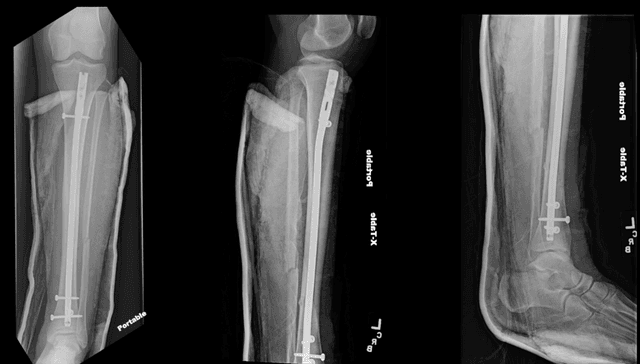

Post-op